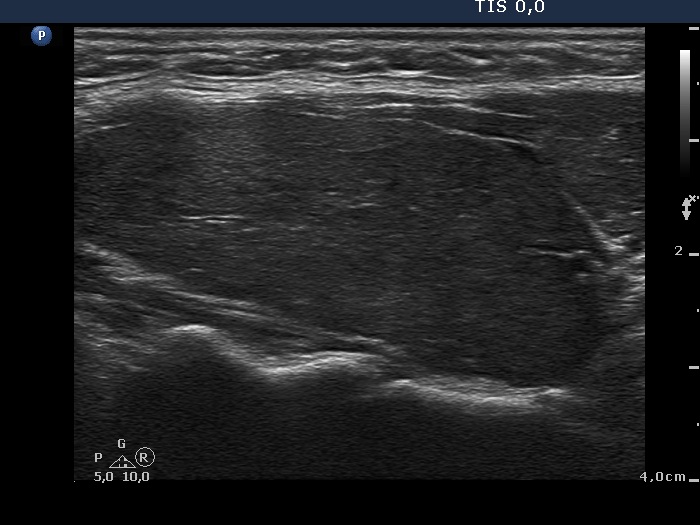

Consecutively operated patients with autoimmune thyroid disease - case 12 (1427) (ultrasonographic picture 6)

Left lobe, longitudinal view. Note the two less hypoechoic areas in the ventral part of the lobe which are probably less influenced by the underlying autoimmune process than other parts of the thyroid.